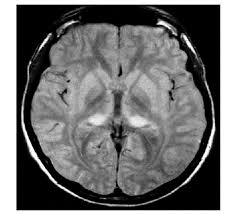

CADASIL/CARASIL

cerebral autosomal dominant/recessive arteriopathy with subcortical infarcts and leukoencephalopathy

NOTCH3 mutations

causes progressive cognitive decline, recurrent ischemic strokes (often lacunar), migraines

MRI features symmetric WM hyperintensities, including in anterior temporal poles